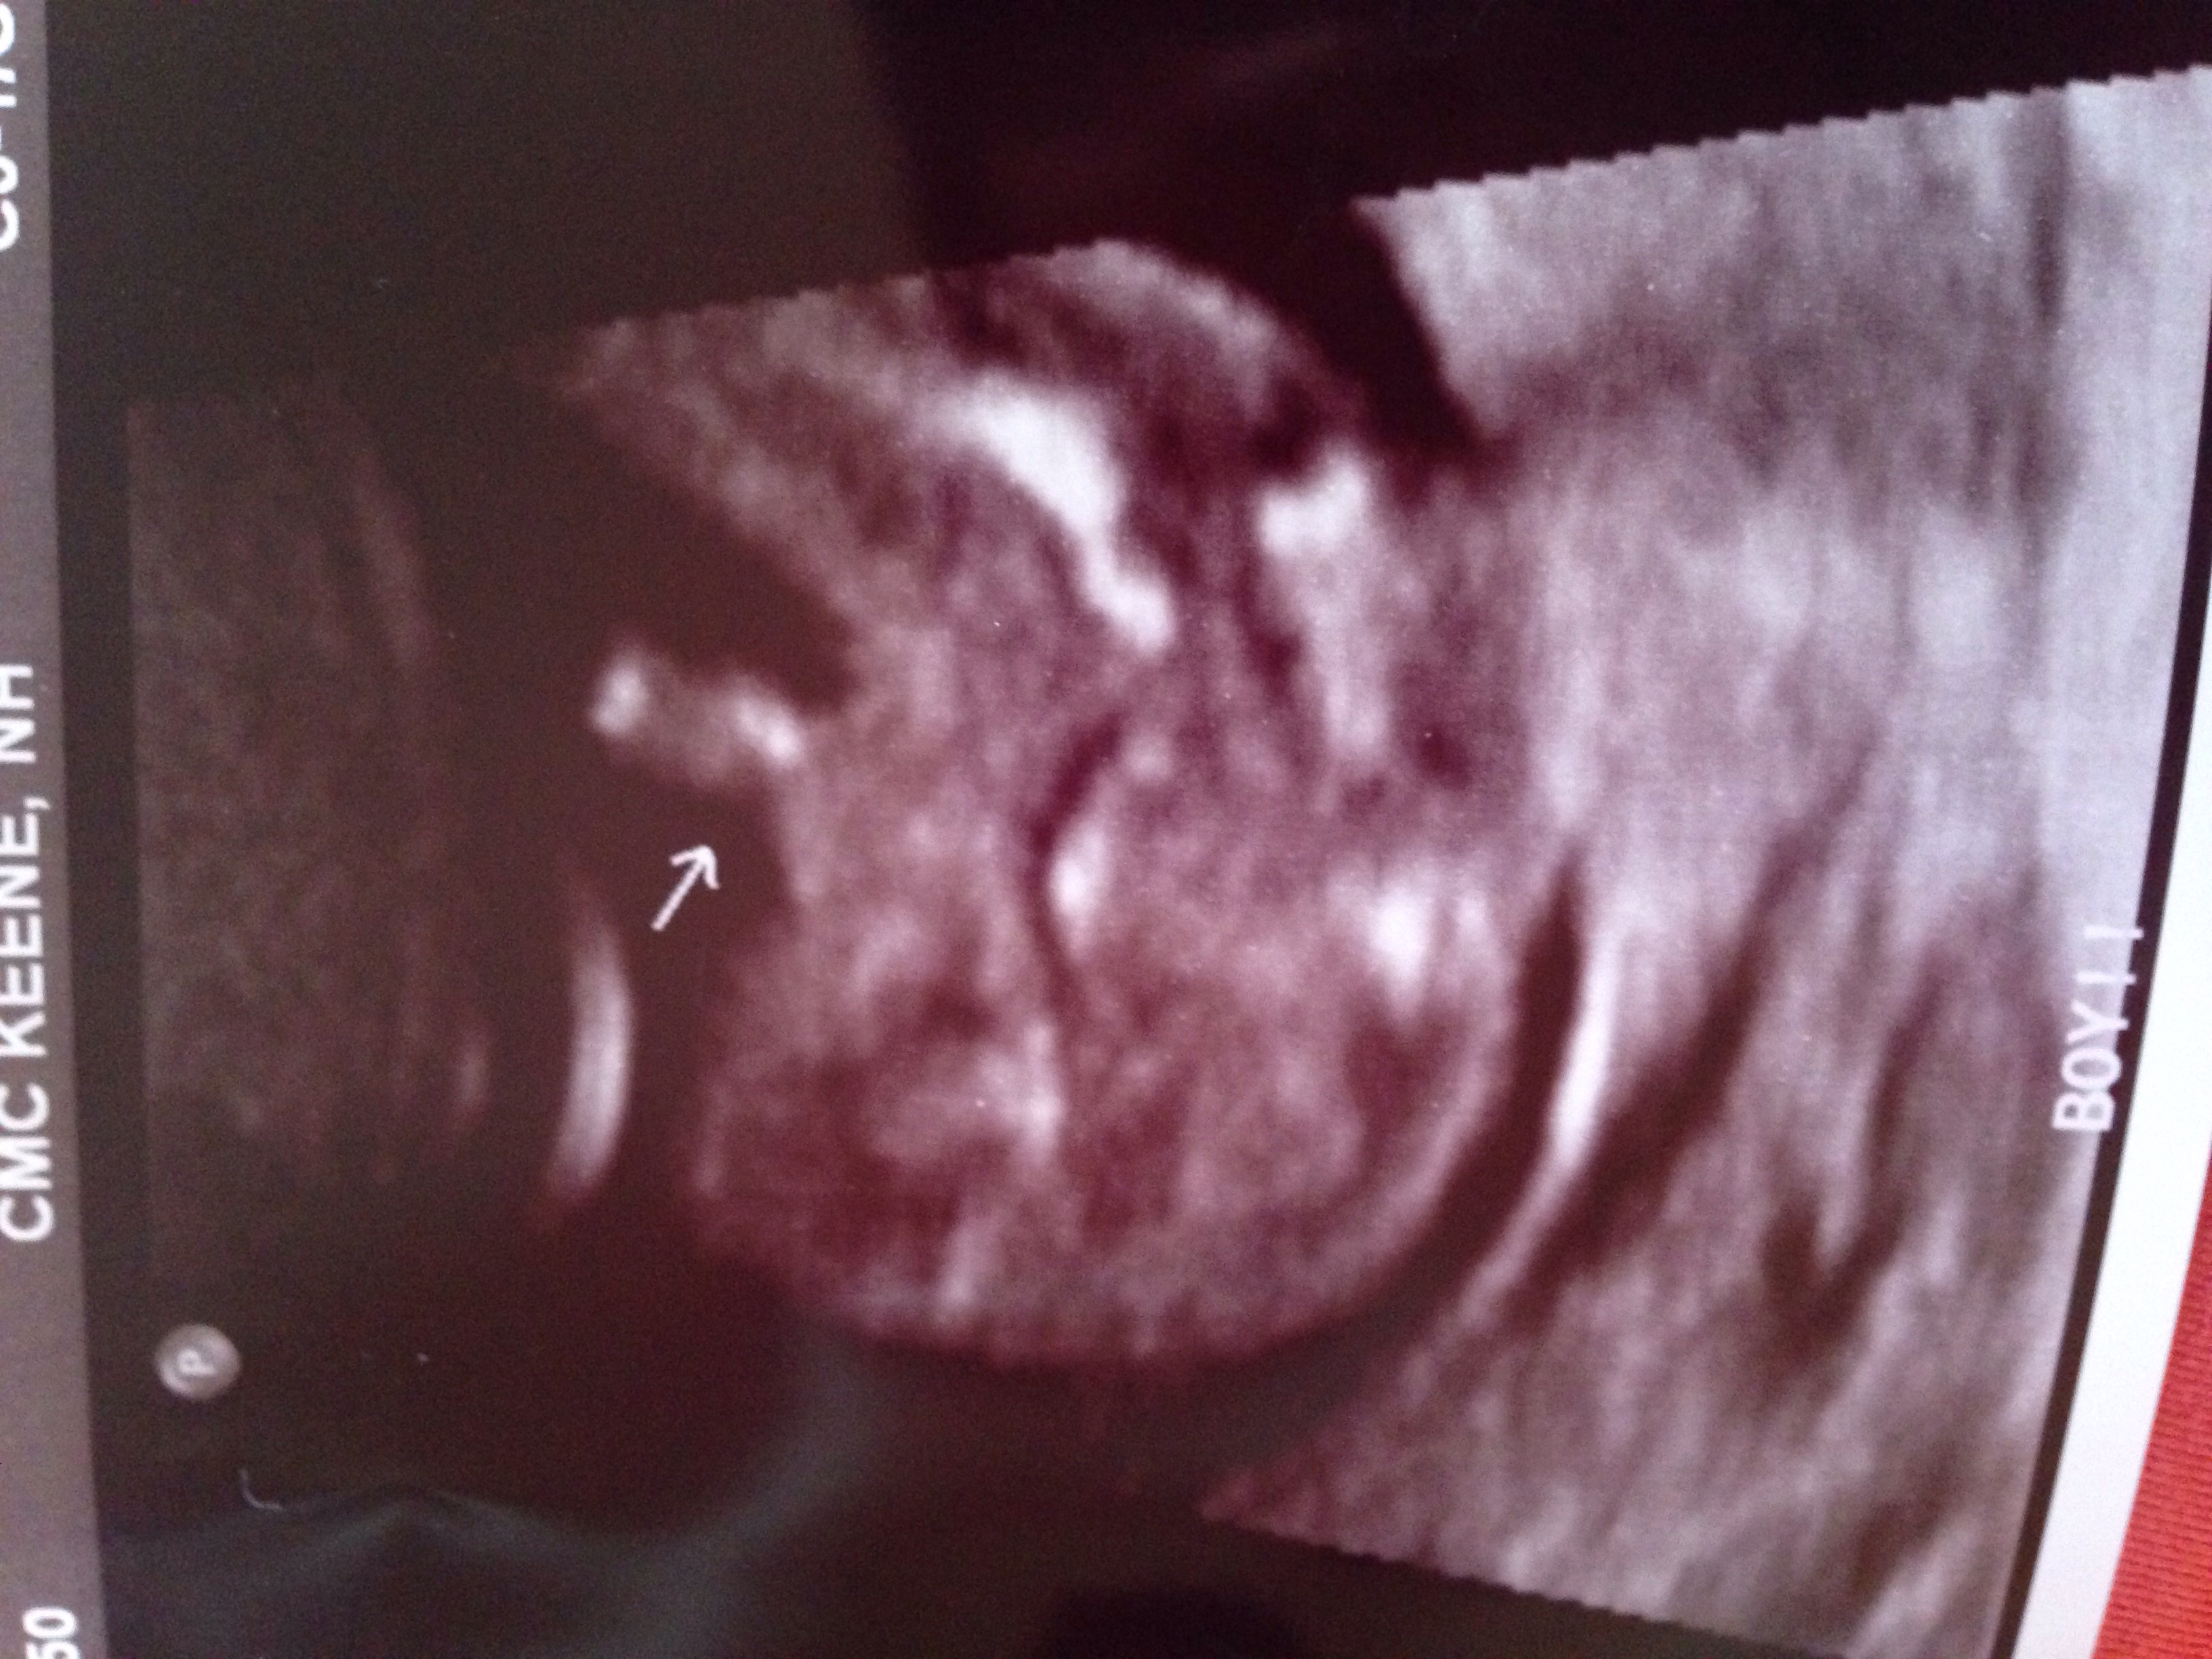

We found out today we are having a bouncing baby boy! Unfortunately I won't know if he's healthy until the doctor calls me later today or tomorrow because she was rushed into delivery. I have heard horror stories about mommies finding out they are really having girls in the delivery room so now it's stuck in my head. Opinions??? The tech seemed VERY convinced he is a he but I need an extra push.

• I would trust your tech. This is one of the many things they are trained for. I am having a boy and the picture I was given is very similar to what you have. The picture is zoomed in and will look bigger then it actually is especially since baby is still pretty tiny (a pound or less). My little guy was only 11 ounces at the time of my ultrasound yet looks huge in most pictures.

• moweltmowelt member

I am having a boy and my sonogram looked just like that. Also it was confirmed by 2 different ultrasound techs at different places and both looked like that. My tech said she knew from a different angle and then moved to that angle for the one to print out for me to prove it was a boy. Your tech knows what they are doing and to me that is definitely a boy.

I would trust your tech more than anyone on this board with no medical background (no offense ladies ;) ) Mine looked just like this and were having a boy. Our tech also mentioned something about seeing through the cord and not a penis, or vice versa, I don't quite remember. If your still unsure, I would ask your doctor before doing an unnecessary scan.

thats probably partially umbilical cord, but your tech was able to tell more than we can by his little pelvic bump, girls are suppose to have a flat pelvic area while boys have a "turtle shell", and depending on the angle of the picture is whether the little turtle has a head or not.